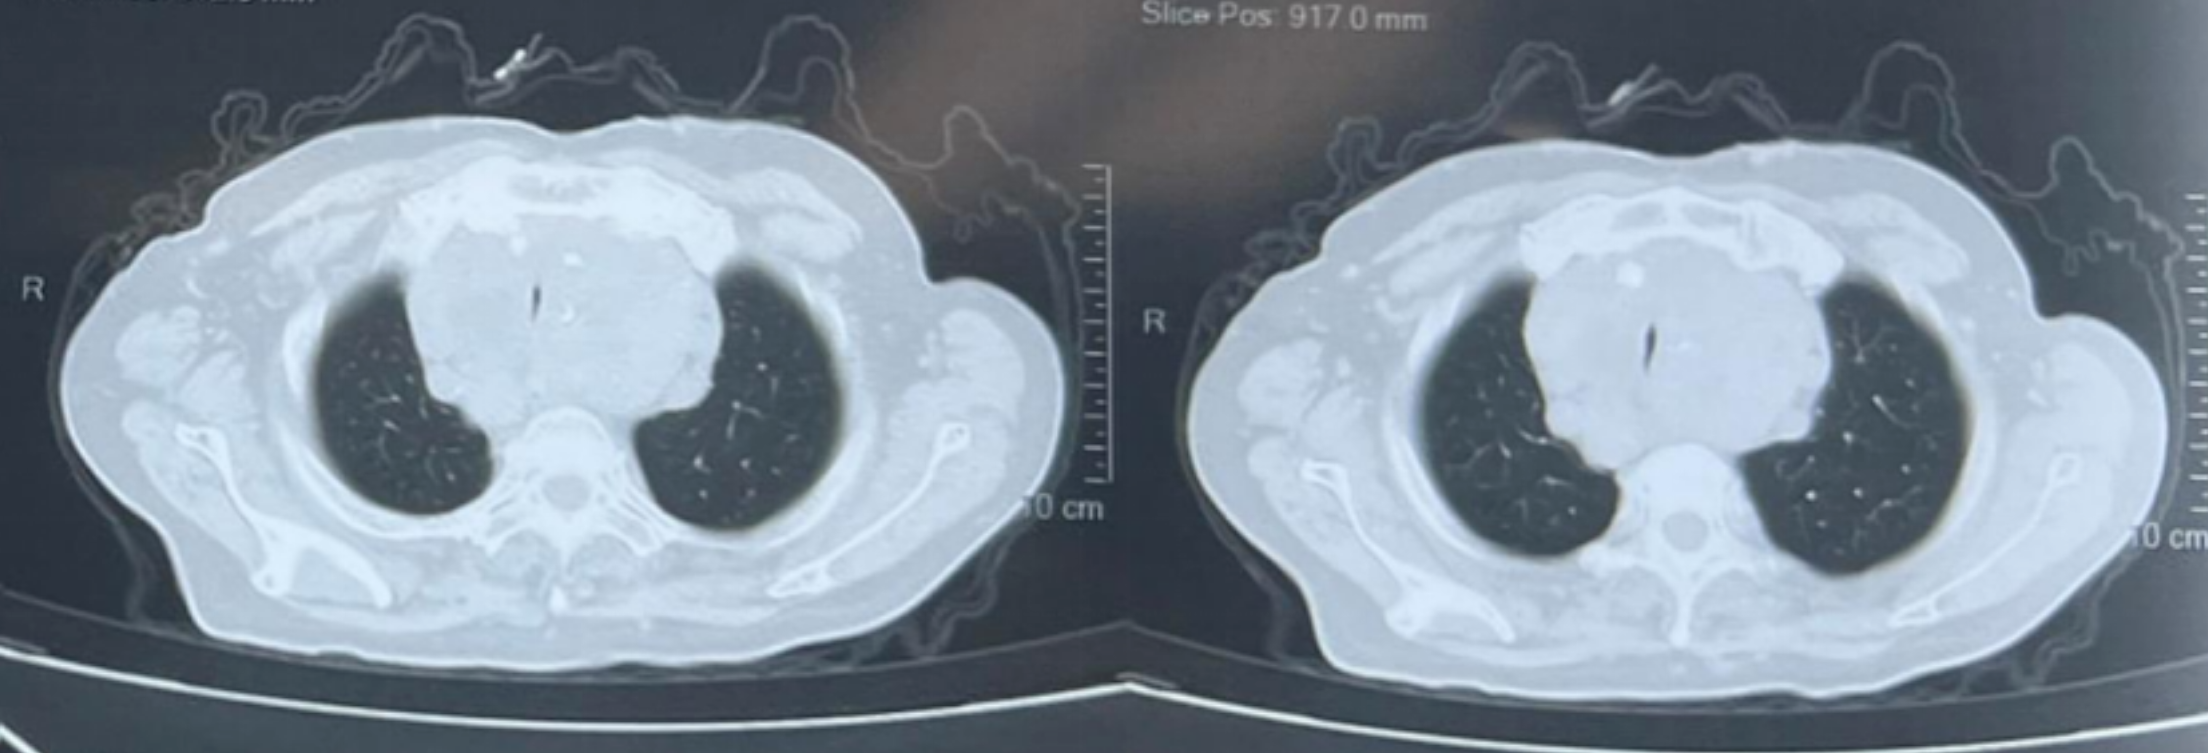

气管镜检查显示声门下气管通畅,声门下约2cm处起见气管外压狭窄,呈刀削样,周围粘膜充血明显,可见毛细血管怒张,狭窄明显处长度约4cm。狭窄处严重影响患者呼吸及日常生活及疾病的诊治,也阻碍了甲状腺肿物的治疗。

对于高龄、多发病灶且伴有严重气道狭窄的患者,气道管理是成败基石。今日分享这例 76 岁高龄患者的硬镜复合手术,重点探讨高频叠加常频通气如何通过“数据证言”,在极端操作下守护生命。